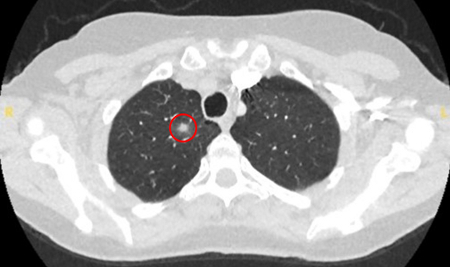

Computed tomography (CT) showing examples of malignant perifissural nodules. Note the spiculated edge of the nodules and the evident retraction of the adjacent fissure. Both resection tissue analyses confirmed adenocarcinoma of lung

From the collection of Dr George Tsaknis, MD, PhD, FRCP(London), MRQA, MAcadMEd, PGCert; used with permission